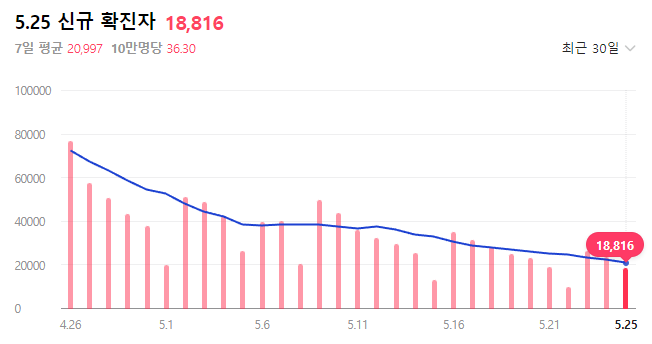

코로나 확진자수가 줄고는 있지만 그래도 하루 만명은 가뿐히 넘고 있습니다. 나는 아니겠지하는 안일한 마음으로 있다가 코로나에 걸려 고생할 수는 없죠. 아픈 기색이 있어 병원에 가고 싶어도 병원에서 코로나에 걸리는 건 아닐까 하는 걱정에 병원방문이 꺼려지는 것이 사실입니다.